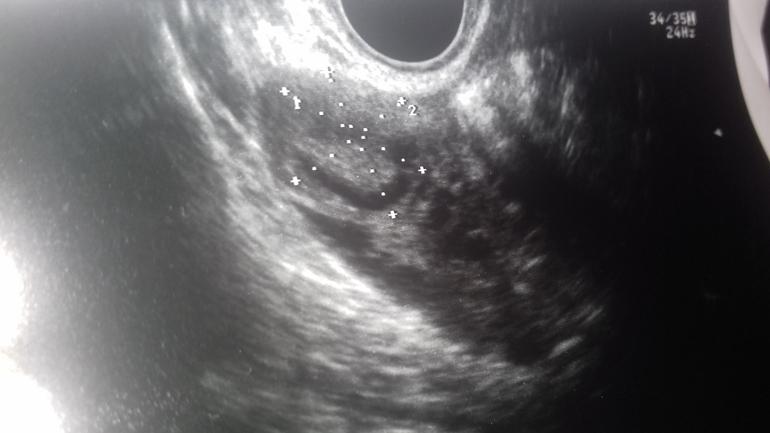

Киста ЖТ или просто ЖТ?

20 ×21×21

Есть жидкость

Добрый день! Это нормальное желтое тело, недавно образовавшееся, скорее всего.

По картинке ощущение, что ЖТ с кровоизлиянием внутрь, а кровоток есть?